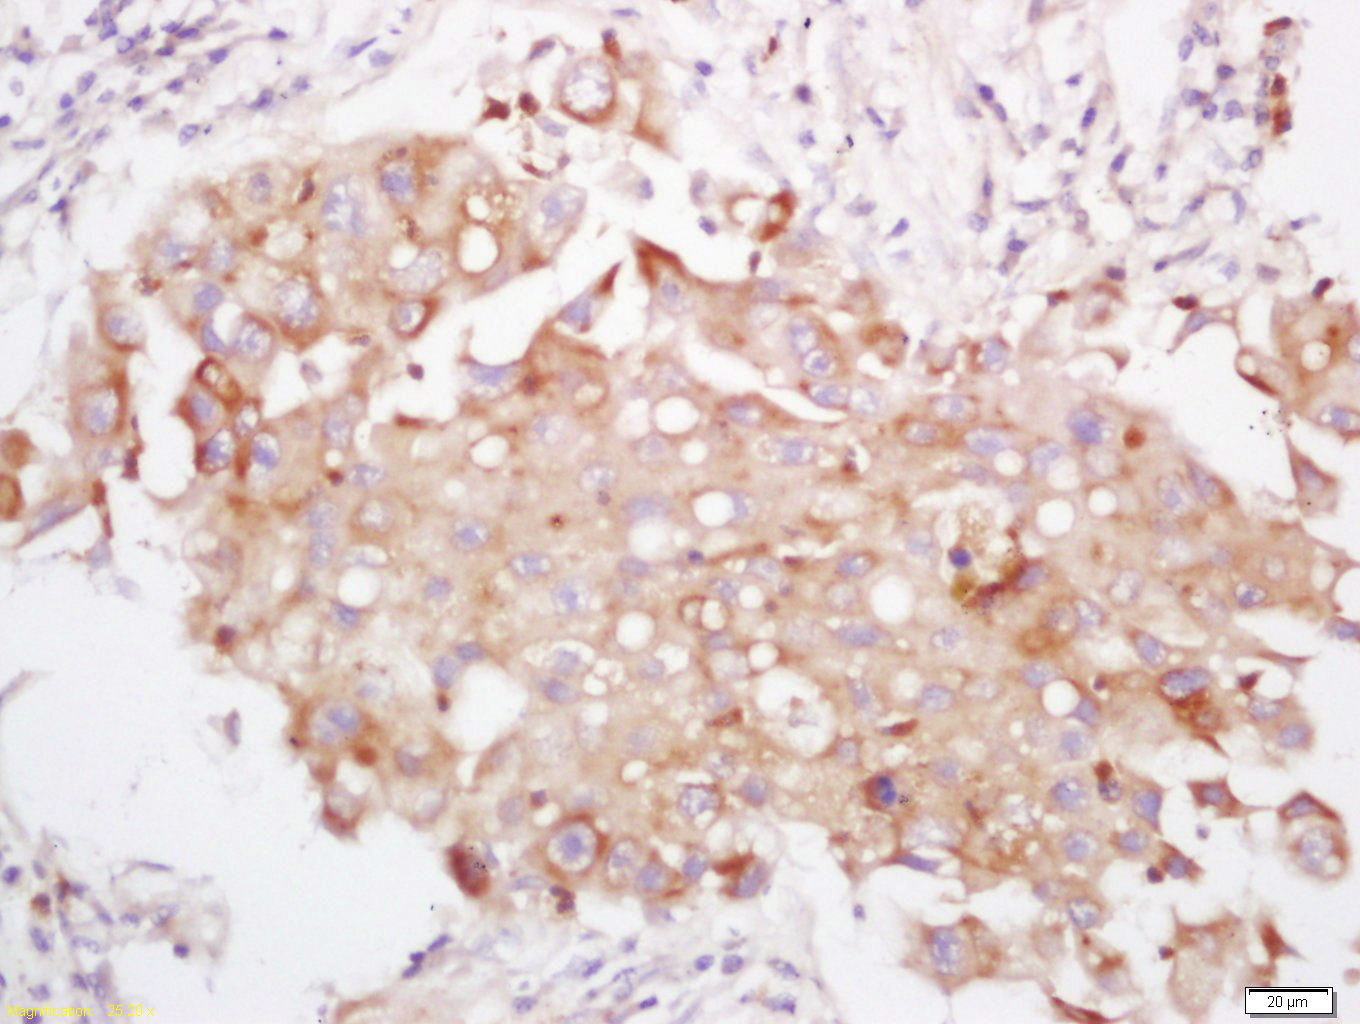

Antigen retrieval: citrate buffer ( 0.01M, pH 6.0 ), Boiling bathing for 15min; Block endogenous peroxidase by 3% Hydrogen peroxide for 30min; Blocking buffer (normal goat serum,C-0005) at 37℃ for 20 min;

Incubation: Anti-PI3 Kinase p110 delta Polyclonal Antibody, Unconjugated(bs-10656R) 1:200, overnight at 4°C, followed by conjugation to the secondary antibody(SP-0023) and DAB(C-0010) staining